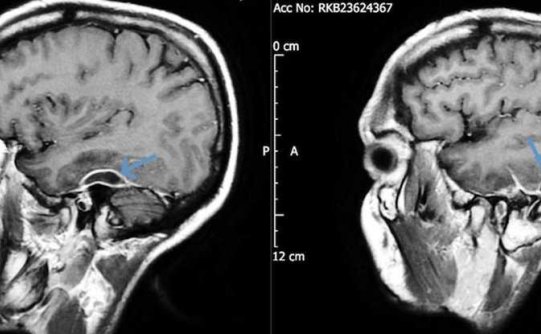

在一份新发表的病例报告中,医生详细描述了一名31岁的健康男子在昏倒后如何被救护车送往医院急诊室。 一到医院,他就癫痫发作,体格检查显示他神志不清,昏昏欲睡,神志不清。 后来,他透露,他已经有好几天感到头痛和恶心,在这段时间里,他很难记住别人的名字,更不祥的是,他承认在过去的五年里,他感到“间歇性的左耳疼痛和听力丧失”。 当医生对这名男子的头骨进行CT扫描时,他们发现他大脑周围的组织中有脓肿,他一只…- 447